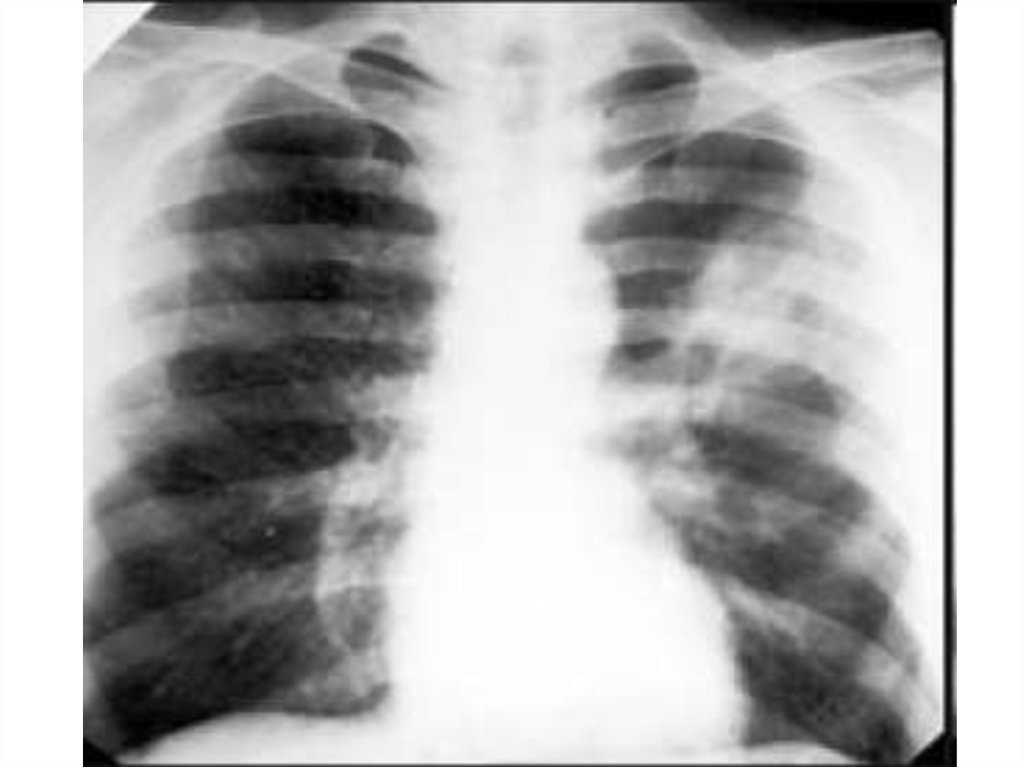

рвота),

• - скрытый (клинические симптомы стихают,

на рентгенографии – ателектаз участка

легкого),

• - период осложнений (развивается абсцесс

легкого, пневмосклероз, тяжелая пневмония).